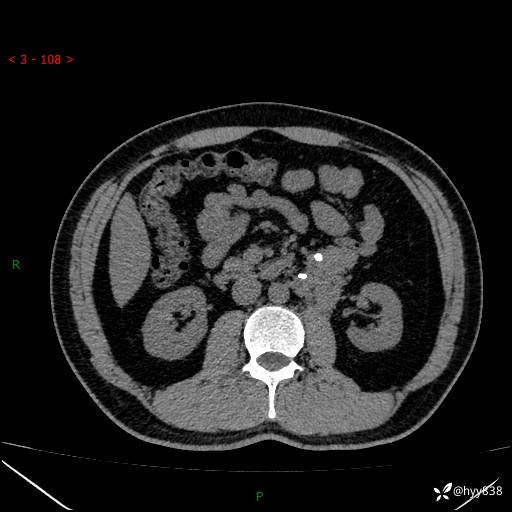

现病史:患者3月余前检查发现左侧腹膜后占位,大小约3.7*4.9cm,平素无腰疼,无肉眼血尿,无尿频尿急等不适,当时未特殊处理,在门诊复查CT提示左侧腹膜后占位,门诊拟“左侧腹膜后占位”收入院。 起病以来,患者精神佳,饮食、睡眠良好,大小便正常,体力体重无明显变化。

腹膜后CT平扫+增强